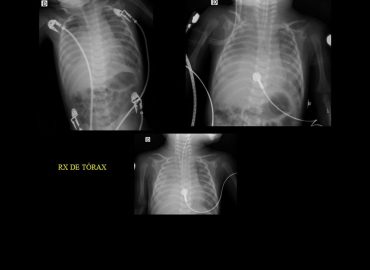

Escasa ganancia ponderal. Crisis de cianosis generalizada